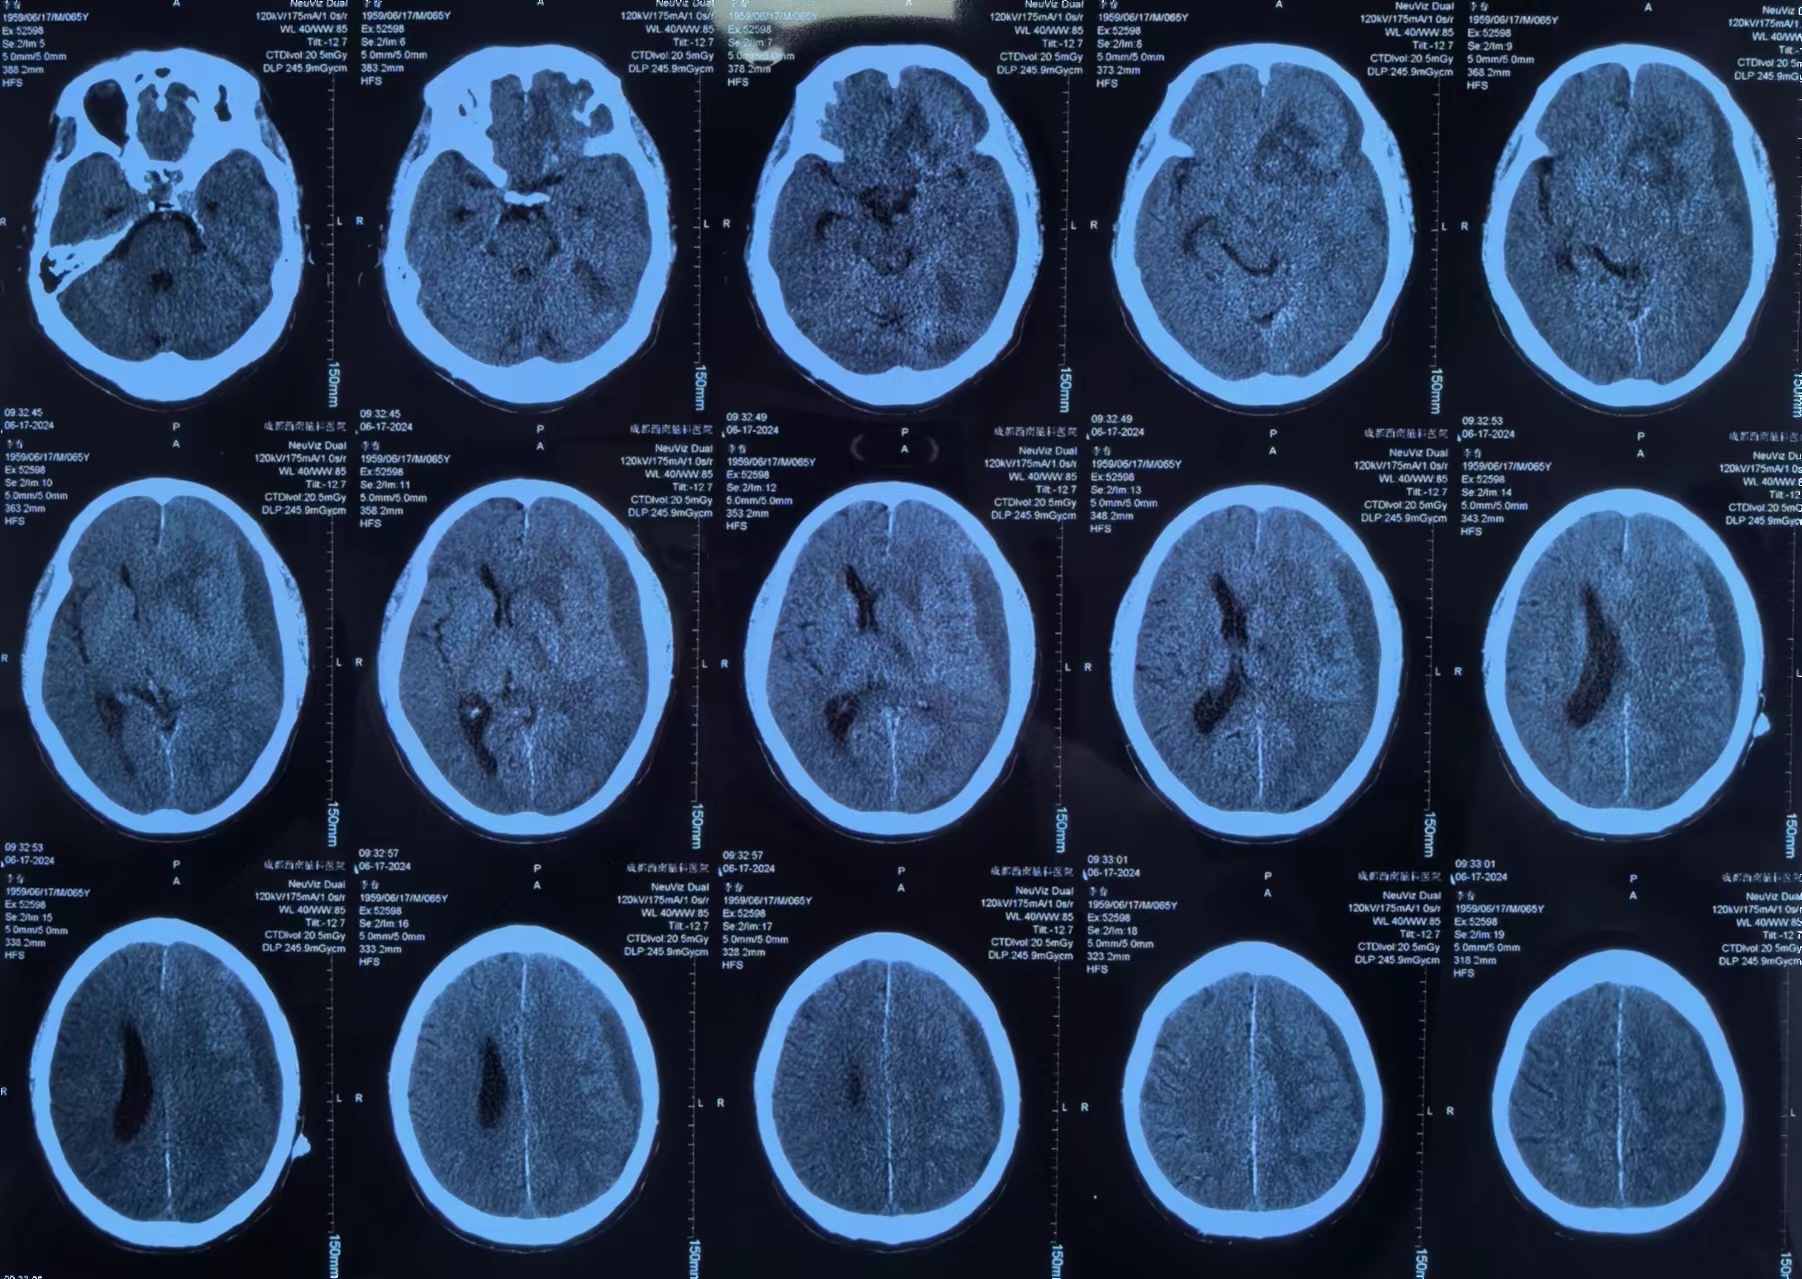

李先生有高血压病史3+年,最高血压166/88mmHg,血压控制一般。10+天前突然出现意识丧失,立即就诊当地医院。李先生送医途中就恢复了意识,但全头部爆炸样胀痛,诊断为脑出血、硬膜下血肿、蛛网膜下腔出血,大脑前动脉中度狭窄,颈内及大脑中动脉均发现动脉瘤。

因当地医院对症治疗一周效果不佳,为求进一步治疗,家人带着李先生辗转来到我院。经左剑主任与李积荣主任联合会诊,认为李先生目前的头痛主要与脑内血肿引起的脑水肿及硬膜下血肿引起的颅高压有关。因患者有多发颅内动脉瘤,最终决定局麻下采用“颅内血肿微创清除技术”清除硬膜下血肿。

李先生手术前

李先生手术后

术后李先生自觉头痛明显减轻,术后第三天复查头颅CT提示:硬膜下血肿基本清除,脑移位恢复正常。